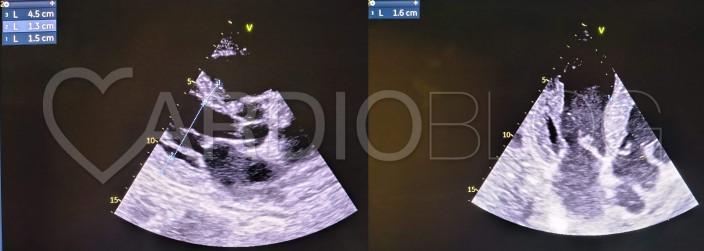

Aktuálisan az EKG-n egy első fokú AV blokk, intra/interatrialis ingerületvezetési zavar (Bachmann nyaláb blokk), bal anterior fasciculus blokkra jellemző extrém bal deviáció, ú.n. pseudoinfarktus mintázat (V1-3-ban gyér R-progressio = R-redukció) és egyes elvezetésekben low voltage mintázat mutatkozott az echocardiographián feltűnő jelentős balkamra hypertrophia, kissé tágabb pitvarok, megvastagodott pitvari septum és megvastagodott, kissé echodensebb billentyűvitorlák mellett.